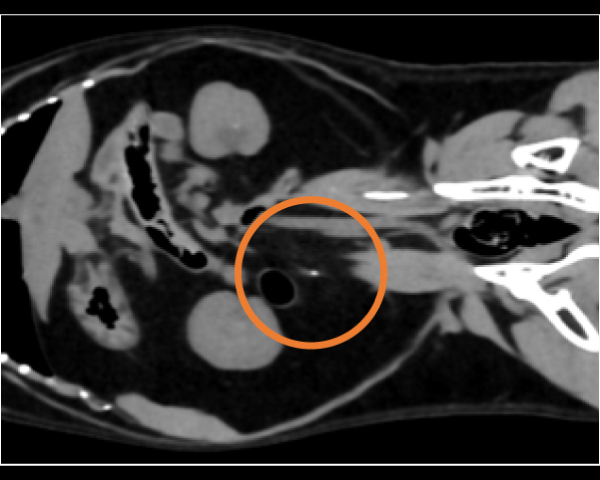

無麻酔CT検査にて異物の確定